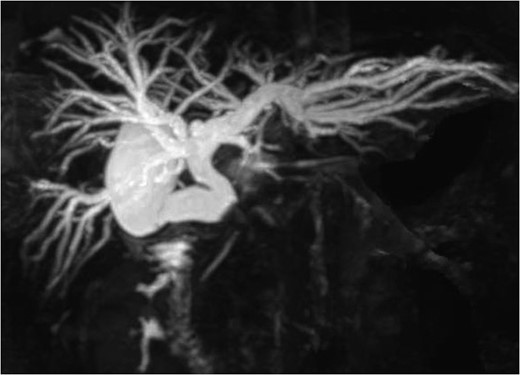

A 36-year-old woman was admitted to our hospital due to appetite loss, nausea, and back pain. A physical examination disclosed right hypochondriac tenderness and obvious jaundice. Laboratory studies showed elevated levels of total bilirubin (9.7 mg/dl), direct reacting bilirubin (6.0 mg/dl), aminotransferase (AST 281 U/l, ALT 362 U/l), alkaline phosphatase (1945 U/l,) and γ-glutamyltransferase (1769 U/l); however, her white blood cell count and C-reactive protein level were within the normal ranges. Magnetic resonance cholangiography revealed that the intrahepatic and common hepatic bile ducts were dilated, and that the gallbladder was distended (Fig. 1). Endoscopic retrograde cholangiography demonstrated a round-shaped filling defect at the confluence of the bile duct (Fig. 2). Based on the findings, the patient was diagnosed with Mirizzi syndrome Type II according to the Csendes classification [1]. Although, the endoscopic removal of the impacted gallstone was unsuccessful, a stent tube was placed for endoscopic retrograde biliary drainage in order to improve the patient’s obstructive jaundice. We planned to perform laparoscopic surgery.

Endoscopic retrograde cholangiography demonstrated a filling defect at the confluence of the bile duct.